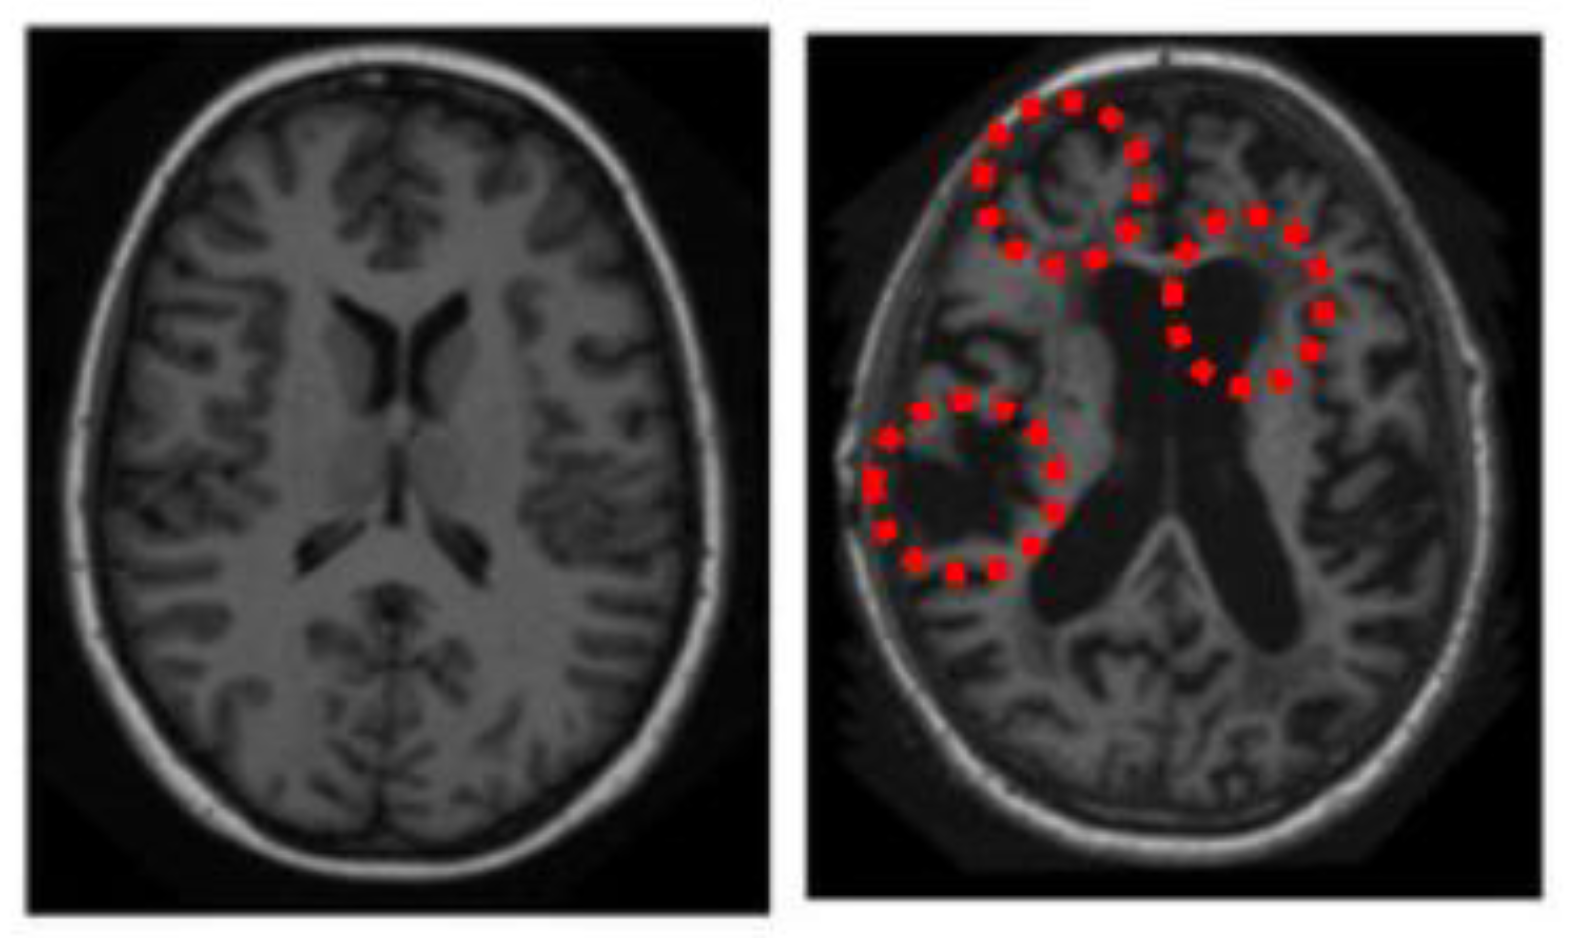

2.3.2. Bottom-Up Saliency Maps (

Elliptical Local Binary Pattern

2.3.3. Final Saliency Map